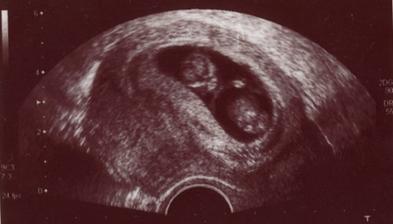

Čekání na Kateřinku... (UZ)

Čekáme holčičku - Kačenku. Dokud jsme jméno vybírali, říkali jsme jí Melounka. I.TP máme 29. 2., II.TP 2. 3. 2008. a III.TP je 13. 3. 2008.